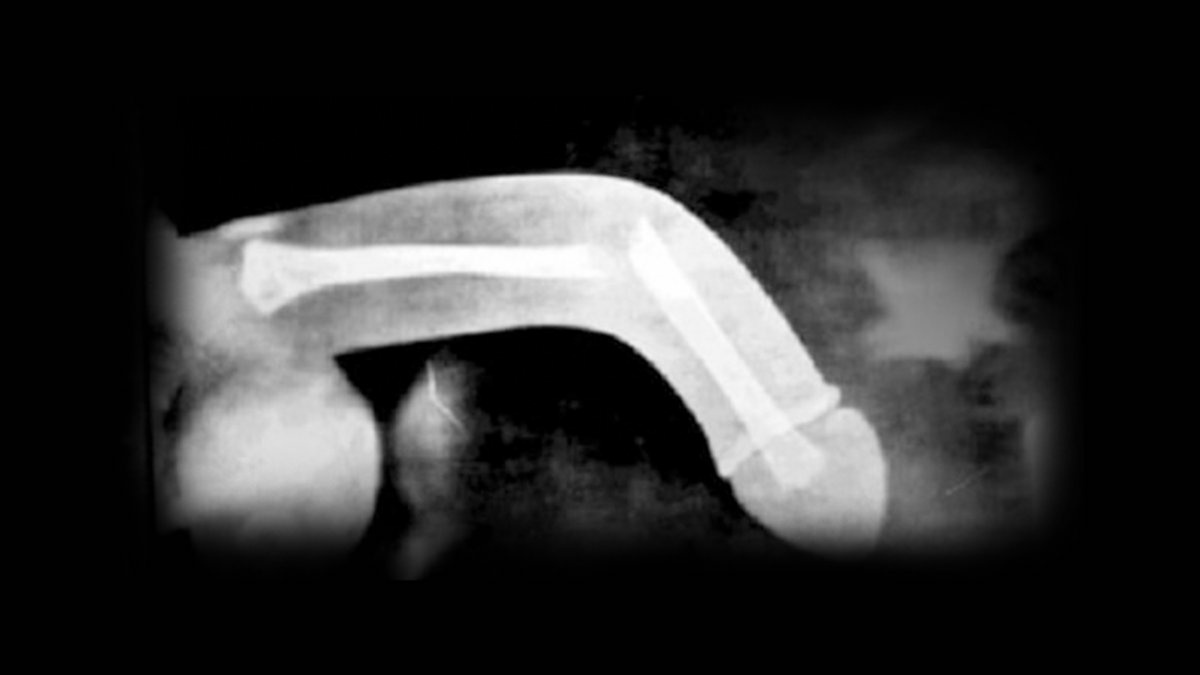

Penis kırılması tıbbi adıyla penis fraktürü, penis ereksiyon halindeyken 'tunika albuginea' adı verilen dokunun yırtılması ve bunun sonucunda kavernöz cisimler içindeki kanın cilt altına çıkmasıdır.

Penis kırılması, penisi çepeçevre saran ve 'tunika albuginea' adı verilen dokudaki yırtıktır.

Anatomik olarak kemik yapı içermeyen penis, içinde kan dolması ile ereksiyonu sağlayan iki tane kavernöz yapı ve idrar kanalını içeren spongioz cisimden oluşmaktadır.

Penis kırılması, kavernöz yapıların ereksiyon esnasında, kanla dolmasına bağlı gergin olduğu durumda travmaya uğraması ve yırtılması durumudur. Travmanın büyüklüğüne göre, spongioz cisim de zarar görür ve idrar yolu yırtılması oluşabilir.